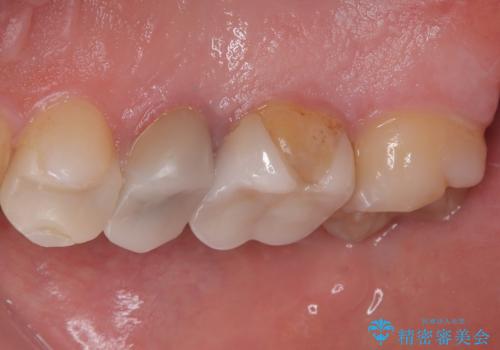

拡大鏡視野下で、セラミックの被せもの、虫歯の除去を行い、オールセラミッククラウンに適した形に整えました。

歯と歯茎の間に圧排糸と言われる糸を入れてシリコーン印象材にて型どりをしました。